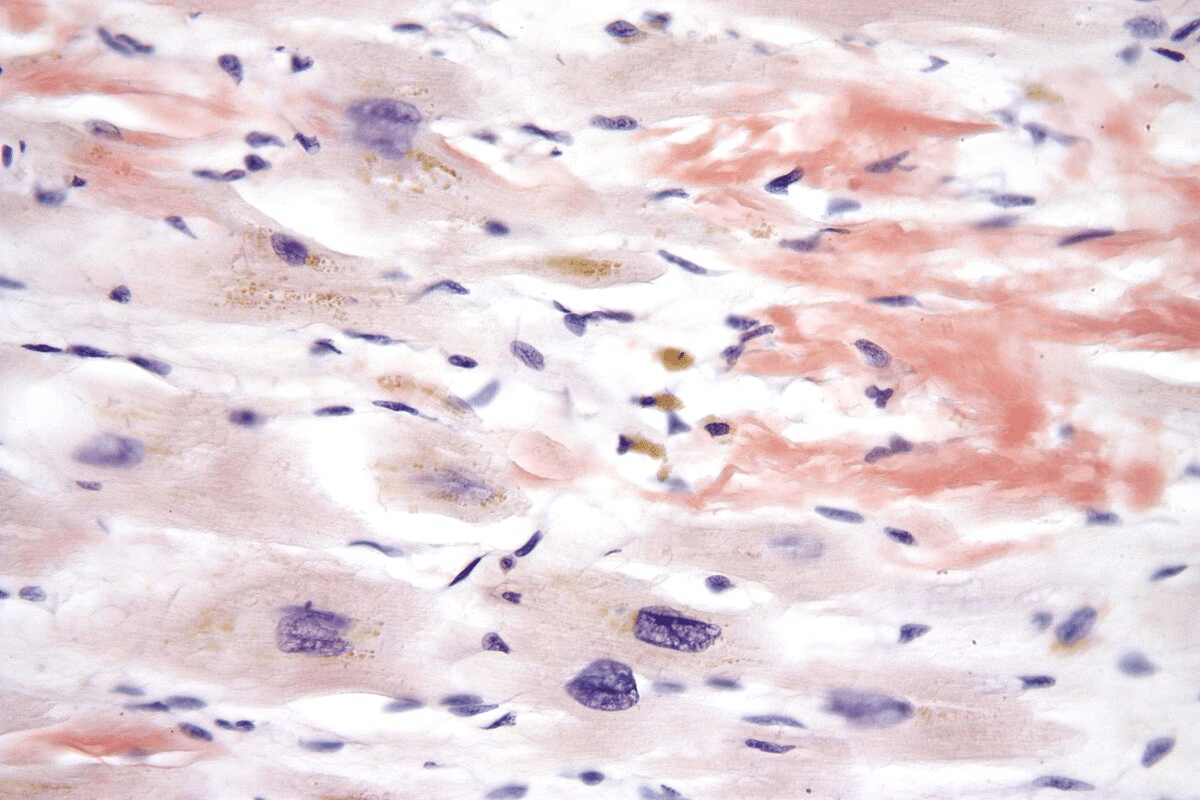

Tissue Biopsy and Congo Red Staining

Tissue biopsy is the top way to diagnose amyloidosis. The biopsy is stained with Congo red dye. Under polarized light, amyloid fibrils show apple-green birefringence.

This special staining is a clear sign of amyloidosis. It shows there are amyloid deposits in the tissues.